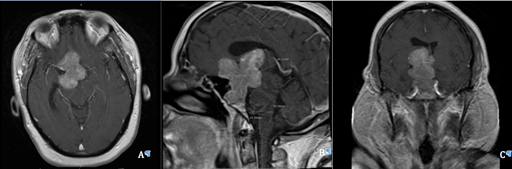

A 44-year-old, right-handed, morbidly obese (BMI=44.75) African-American female smoker initially presented with worsening daily frontal headaches, vision difficulties, nausea, and vomiting for four years prior to surgical intervention. Due to elevated prolactin levels, the patient was managed initially with bromocriptine therapy, which she eventually became unable to tolerate. After failing medical therapy and symptoms worsened, she was referred to neurosurgery. History and physical exam were otherwise unremarkable. Imaging revealed the presence of a giant pituitary adenoma (Figure 1). The decision was made to surgically resect the pituitary adenoma transsphenoidal ly through an endoscopic endonasal approach (EEA).

Figure 1 Pre-operative MRI T1 with contrast axial (A), sagittal (B), and coronal (C) views showing a large multilobular mass with lengthy extensions, vascular encasement, bone involvement, and mass effect.

Pre-operative magnetic resonance imaging (MRI) with and without contrast revealed a large mass arising from the pituitary gland with lengthy extensions, vascular encasement, bone involvement, mass effect causing optic nerves/chiasm compression, and hydrocephalus (Figure 1). The lobulated mass lesion arose from the sella with suprasellar extension predominantly towards the right, with measurements of 6.8x5x3.5 cm giving the impression of a giant pituitary adenoma. Lateral extension into the cavernous sinuses was also noted. The clivus and sphenoid sinuses also demonstrated tumor involvement. Mass effect upon the right lateral and third ventricle produced a midline shift and obstruction causing dilatation of the right lateral ventricle and left frontal horn.